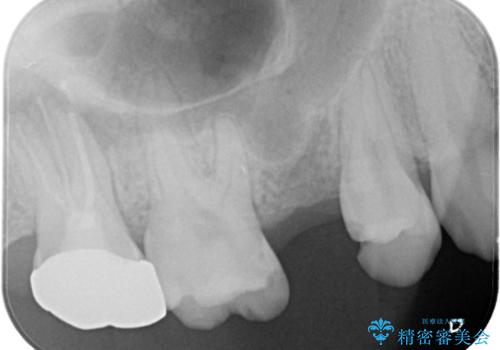

- 数年前に他医院で抜歯したままで過ごし、今回歯を入れたいとのことで来院された患者様です。

治療回数を短くしたいと1DAYインプラントを希望されました。

インプラント埋入手術は1回で全て行い、2ヶ月後にはセラミック治療で、審美回復と機能回復をしました。